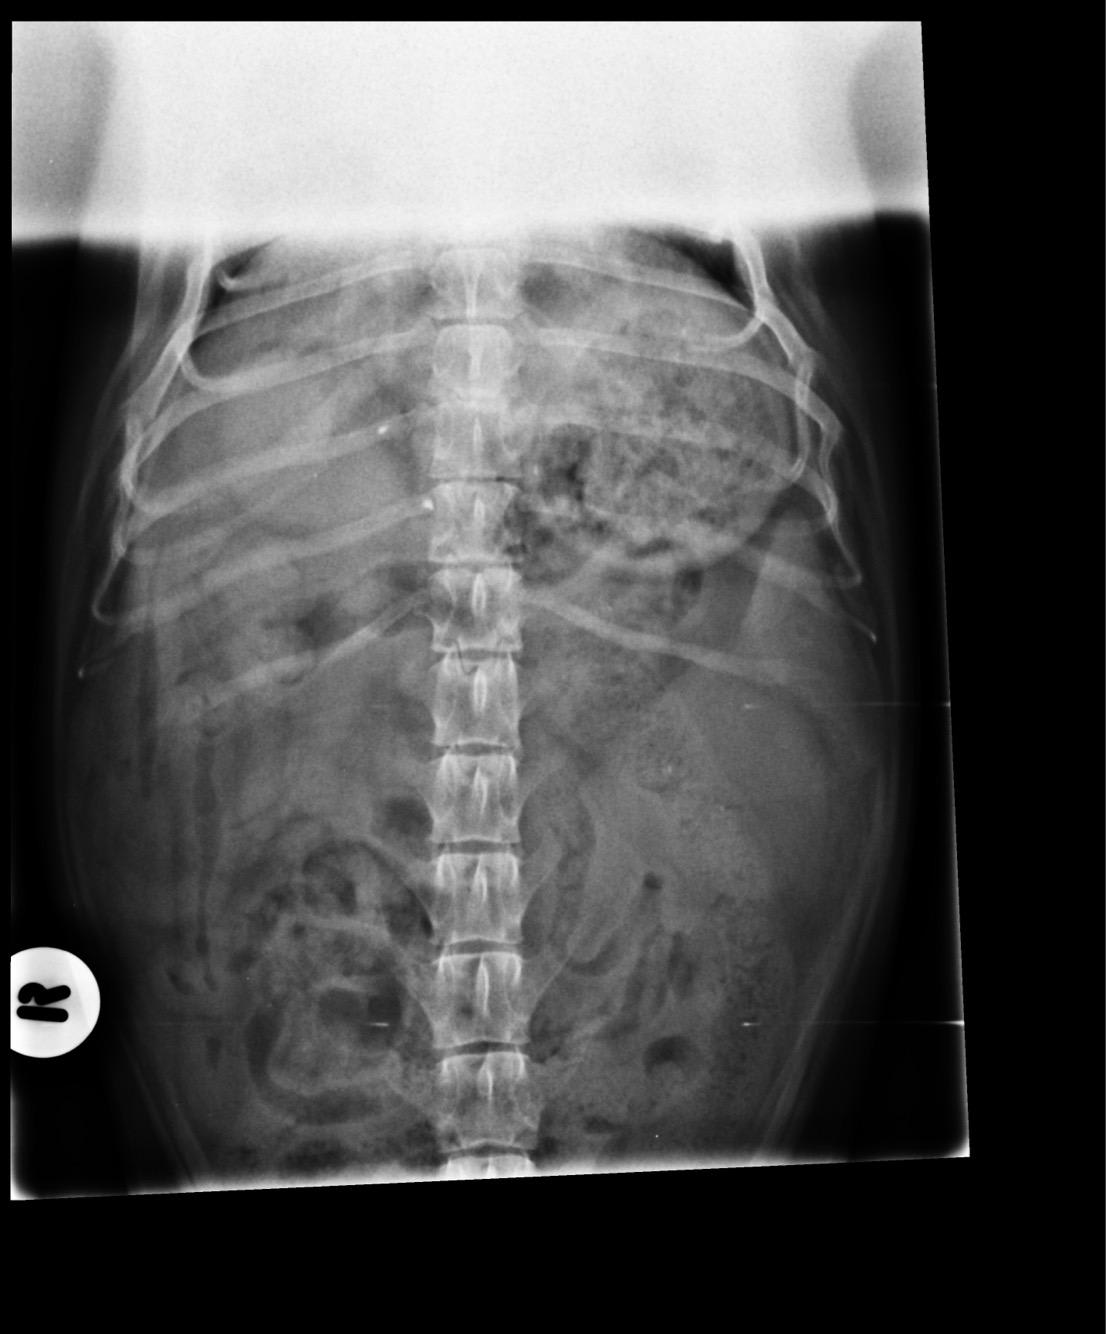

Are my dog's X-rays enough to diagnose a spleen hemangiosarcoma?

Pet's info: Dog | Dachshund | Male | neutered | 6 years and 6 months old | 20 lbs

Could you please advise as to whether this is adequate imagining to determine a sarcoma? Could it possibly be a hemangiosarcoma?

There is possibly a mass on the left side attached to the spleen, but these x-rays are not sufficient to tell. If there is a mass on the spleen, the most likely possibilities are hematoma (basically a bruise), hemangioma (a benign tumor) and a hemangiosarcoma. So yes, if there is a mass there is could be a hemangiosarcoma, however ultrasound would be needed to get a better view, and ultimately the mass (likely the entire spleen) would need to be removed and biopsided to get a specific diagnosis.